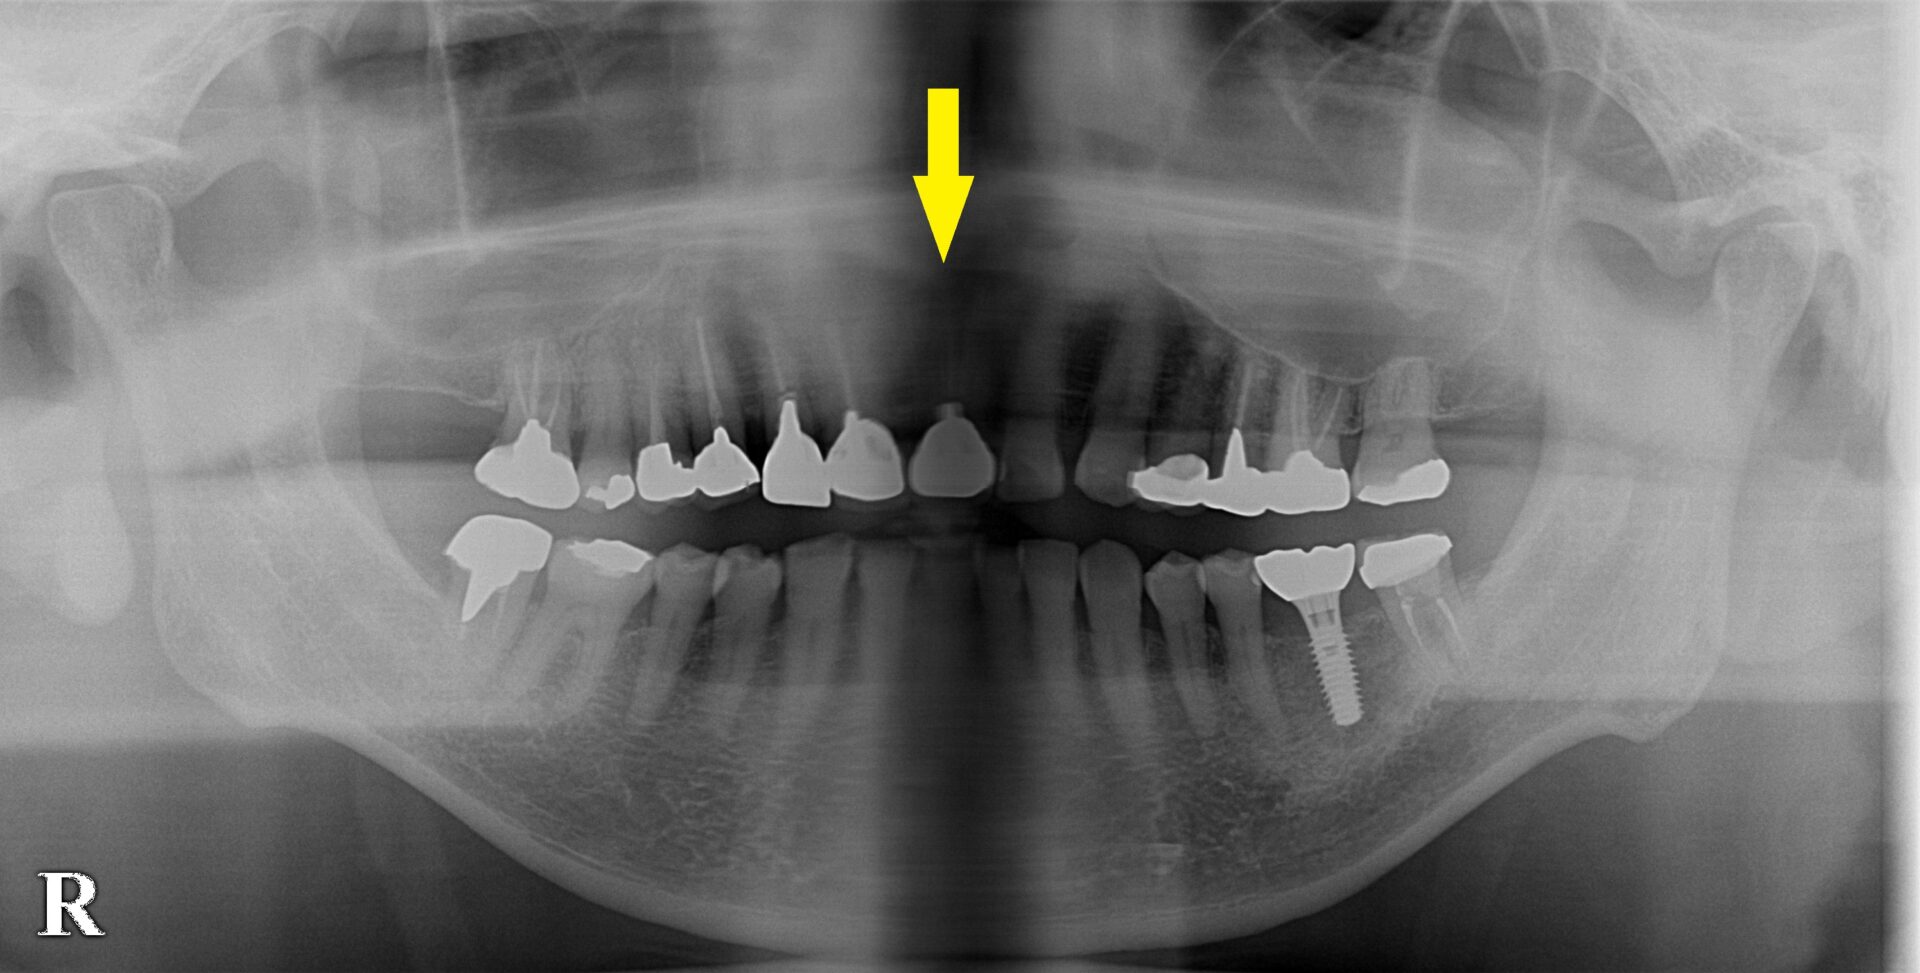

レントゲン写真、CTを撮影してみると、周囲の骨の状態は良好でしたので、この場合は、抜歯即時インプラント埋入をお勧めしました。

下の写真下段が手術前後のCTです。